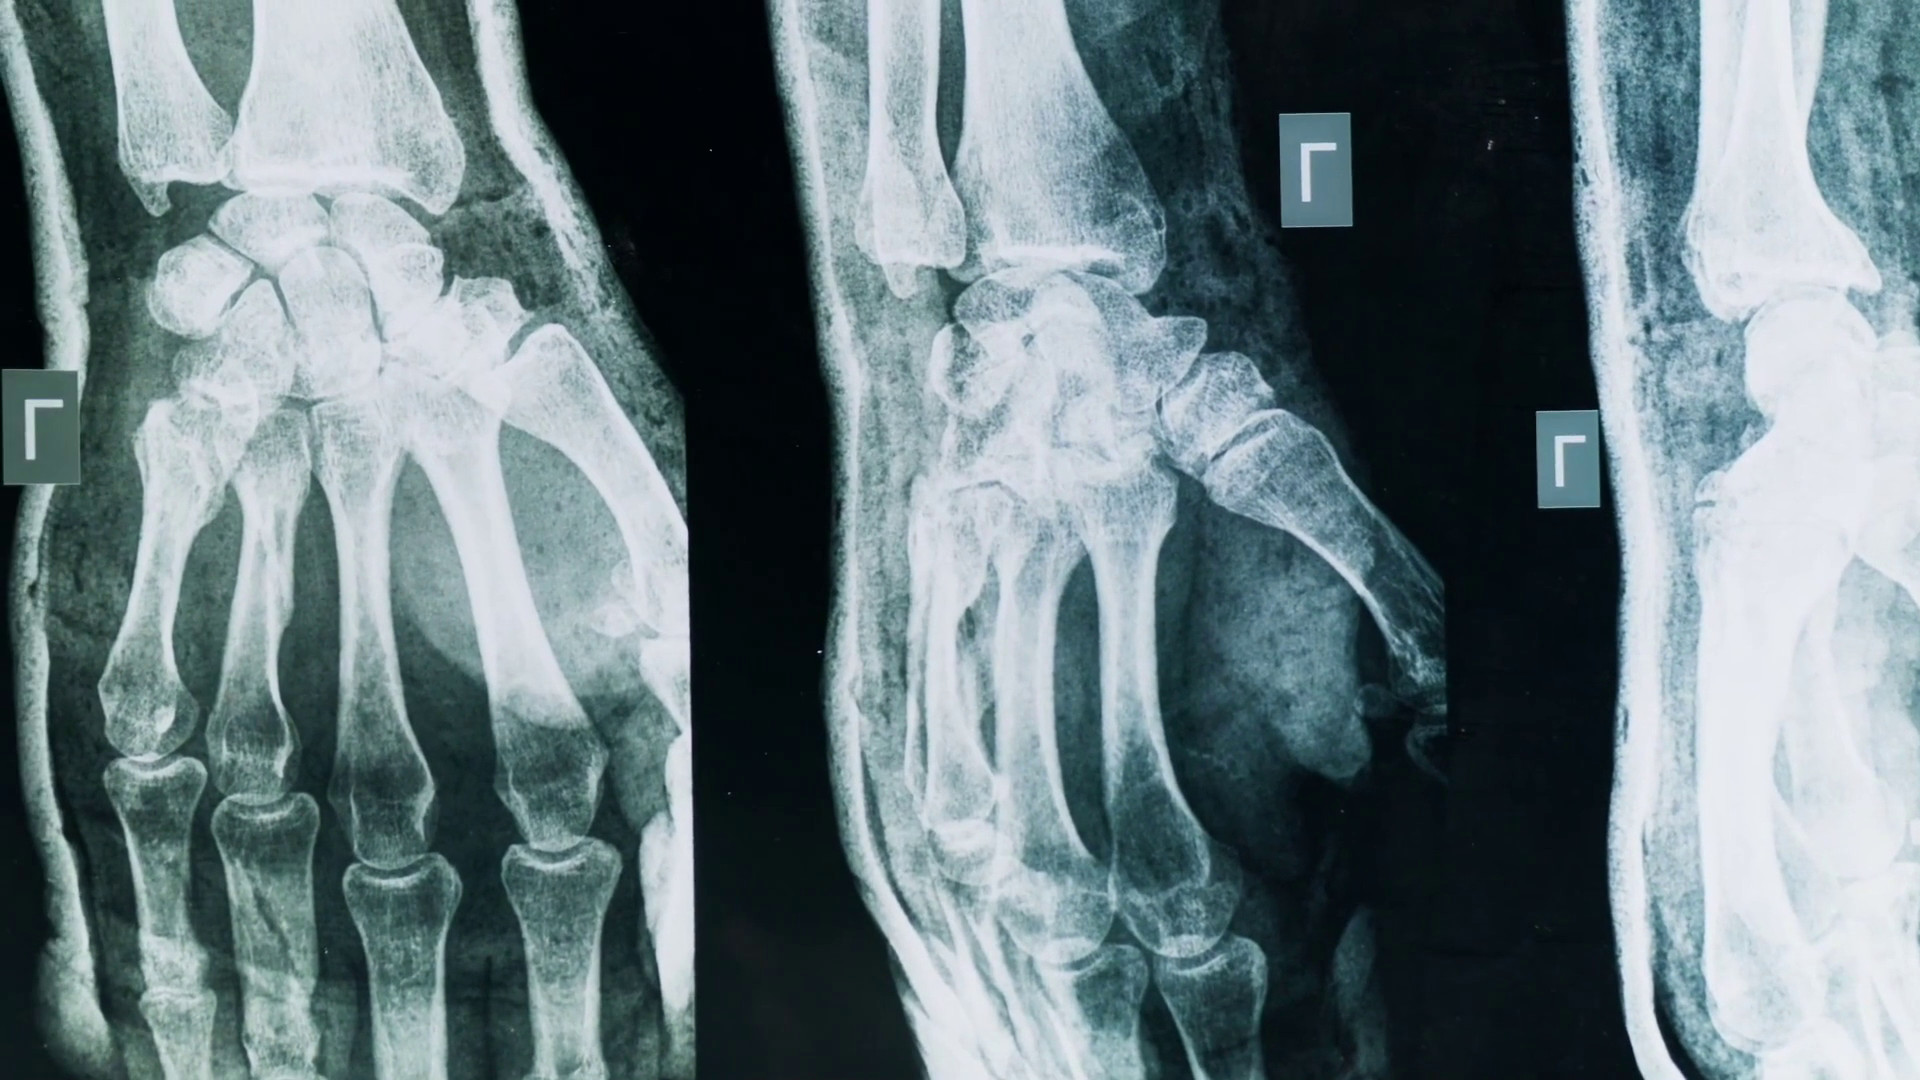

MILANO (ITALPRESS) – Artrite e artrosi sono tra le più diffuse malattie articolari: due condizioni che condividono alcuni sintomi ma differiscono per causa, evoluzione e trattamento. Con il termine artrite si intende un gruppo di malattie infiammatorie delle articolazioni: può avere origine autoimmune, infettiva o essere legata ad altre malattie sistemiche. Una delle forme più studiate è l’artrite reumatoide, che si manifesta con infiammazione persistente, dolore e gonfiore e può colpire più articolazioni in modo simmetrico: in Italia si stima che l’artrite reumatoide colpisca circa 400mila persone. Al contrario l’artrosi è una malattia degenerativa, caratterizzata dall’usura della cartilagine articolare, alterazioni della struttura ossea sottocartilaginea e cambiamenti delle cellule articolari. È la forma più comune di malattia articolare: i principali fattori di rischio sono l’età, il sovrappeso, il sovraccarico articolare, traumi pregressi, predisposizioni genetiche.“Quando una persona arriva con dolore a un’articolazione questo si definisce un’artralgia, quindi un semplice dolore; se c’è un’articolazione degenerata parleremo di artrosi, mentre se è infiammata parleremo di artrite. Sono dolori di tipo molto diverso: quello dell’artrosi peggiora con l’uso e il carico dell’articolazione, quello dell’artrite con l’inattività”, ha dichiarato Carlo Selmi, responsabile dell’unità operativa di Reumatologia e Immunologia clinica presso l’ospedale Humanitas di Rozzano, intervistato da Marco Klinger per Medicina Top, format tv dell’agenzia di stampa Italpress.